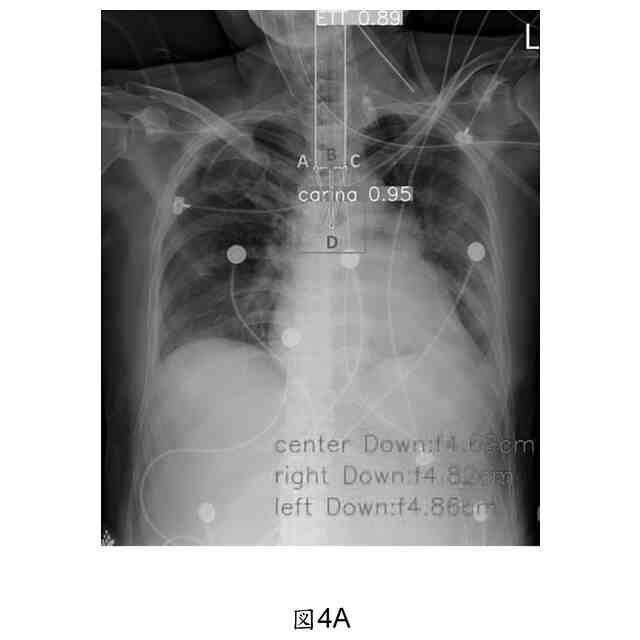

当該位置評価モジュールは、気管内チューブ先端と気管カリーナとの距離を測定し、識別した気管内チューブ先端の注釈境界ボックスの下端から、左端と右端の座標点を選び出して、関数で、2点間の中間点を計算し、それが、ユークリッド距離公式で当該3点と気管カリーナの距離値を利用して、計算した最も短い距離を選び出し、また、当該距離に対して、画像のピクセル値を、対応する実際の距離値に変換する、ことを特徴とする、請求項1に記載される気管内チューブの位置異常な警告装置。

当該位置評価モジュールは、気管内チューブの先端位置が、気管カリーナより低い時、或いは、気管内チューブ先端と気管カリーナとの距離が、3cmより小さい時や5cmより大きい時、アラームをトリガーする、ことを特徴とする、請求項1に記載される気管内チューブの位置異常な警告装置。

【0008】

当該方法には、画像の高さと幅が含まれる、トレーニングデータセット画像のオリジナルサイズを定義する、ステップ1と、処理待ちの入力画像を受信する、ステップ2と、入力画像のサイズとトレーニングデータセット画像のサイズとの比率であるスケーリングrを計算し、比較的に小さい値を選択してスケーリングとする、ステップ3と、計算したスケーリングrに基づいて、入力画像のピクセル値を、トレーニングデータセット画像に対応する実際の距離値に変換する、ステップ4及び、変換された実際の距離値を、画像分析とマークに利用し、例えば、物体の間の距離計算とマークである、ステップ5と、が含まれる。

本発明は、上記らの目的を達成するため、気管内チューブの設置位置の正確性を監視する、気管内チューブの位置異常な警告装置であって、患者の胸部X線の画像素材を収集する、監視モジュールと、当該監視モジュールに接続されて、当該監視モジュールから入力された当該胸部X線の画像素材を受信し、人工知能(Artificial Intelligence, AI)計算モデルで、画像上の気管カリーナ(tracheal carina)や、気管内チューブ(endotracheal tube, ETT)及び気管切開チューブ(tracheostomy tubes)の存在を識別して、その位置を注釈する、物件検知モジュールと、当該物件検知モジュールに接続され、当該物件検知モジュールが、気管カリーナや気管内チューブの存在を検知した時、当該人工知能計算モデルの判断結果の注釈位置に基づいて、自動的に、気管内チューブの先端と気管カリーナとの距離を測定し、また、求めた距離の数値に基づいて、気管内チューブの位置適当性に対して、評価結果を生成し、当該評価結果において、当該気管内チューブの位置が、正確範囲内に位置しない時、アラームをトリガーする、位置評価モジュール及び、当該位置評価モジュールに接続され、当該物件検知モジュールと当該位置評価モジュールの判断結果を受信して、警告信号を発して、また、物件の注釈結果や気管内チューブの位置適当性の当該評価結果を表示する、表示モジュールと、が含まれる。